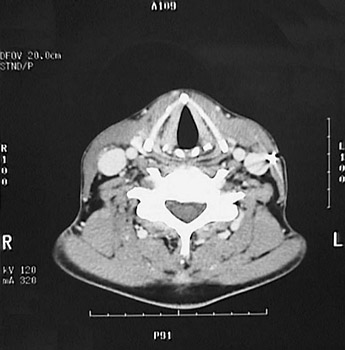

This is a normal axial head and neck CT scan demonstrating the thyroid cartilage and arytenoid cartilage and focal fold and larynx and C5 and spinal canal and internal jugular vein and common carotid artery and trapezius muscle and splenius capitis muscle and levator scapulae muscle and sternocleidomastoid muscle.